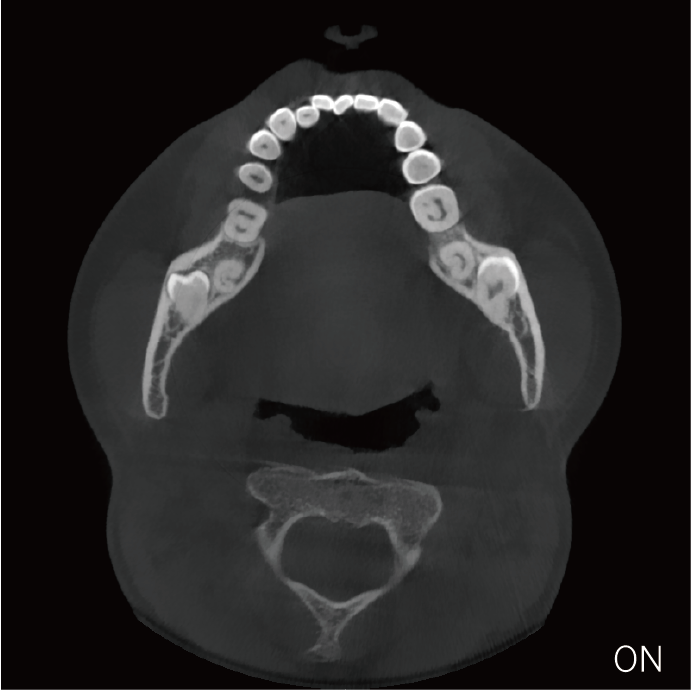

超能去伪 至臻影像

临床样片